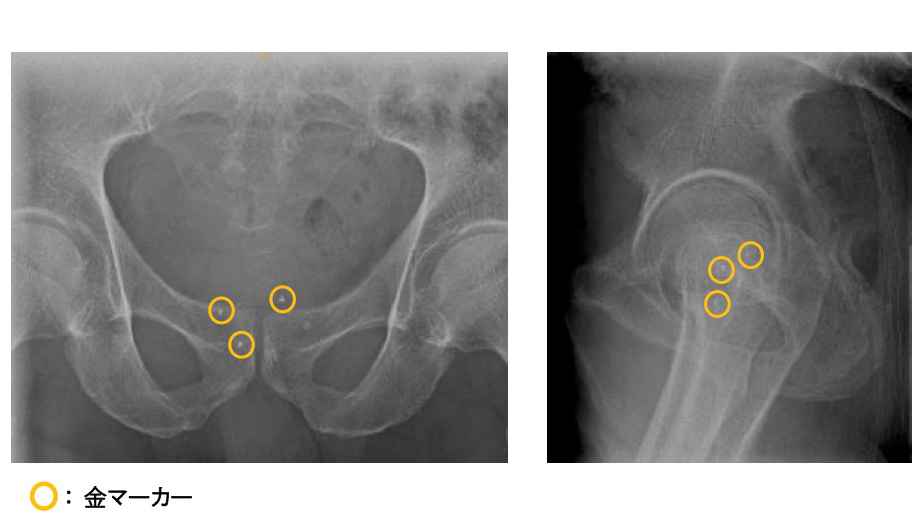

2.3つの金マーカによる高精度放射線治療

陽子線治療は毎回同じ位置に照射することが⼤切ですが、前⽴腺は体内で微妙に動きます。そのため治療前に前⽴腺内に⾦マーカーを挿⼊し、3次元構造の正確な把握に役⽴てます。

通常は1箇所のところを当院では3箇所にマーカーを留置して、安全で正確な治療を⾏っています。